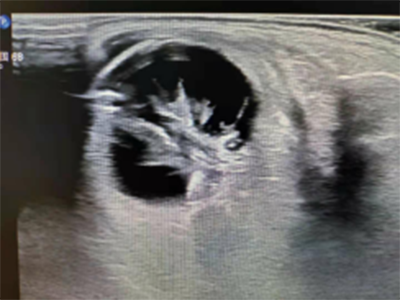

上圖是1例眼外傷患者眼內(nèi)機(jī)化膜形成,彩超檢查:膜狀回聲內(nèi)未檢測(cè)到血流信號(hào)